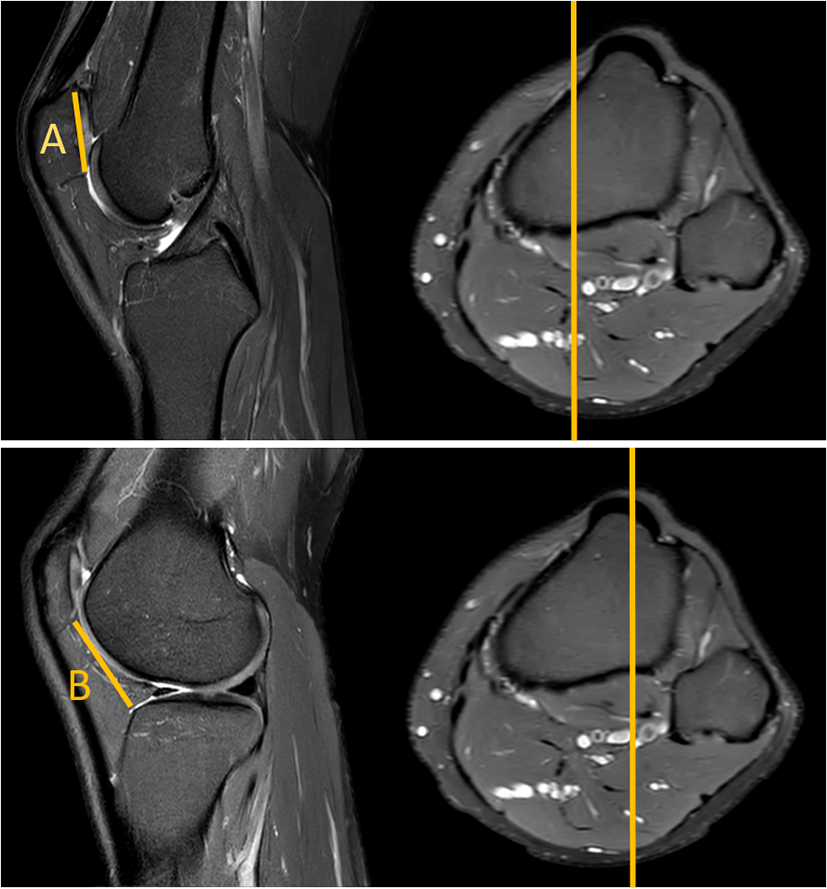

The MRI-based assessment of CD was performed using both the standard single-slice method, and the new two-slice method. The single slice assessment of CD was performed on a single sagital MR-images, utilizing the plane with the maximum length of the articular surface of the patella (Fig. 2). The two-slice method firstly measured the length of the articular surface of the patella at its maximum length (similar to Method 1), and then assessed the distance to the anterior angle of the tibial plateau in the sagittal plane going through the center of the tibial tuberosity (Fig. 3).

Fig. 2

MRI true sagittal view. Caton–Deschamps (CD) index measurement with one slice. B distance from the patella to the tibia and A patellar cartilage length. CD: B/A